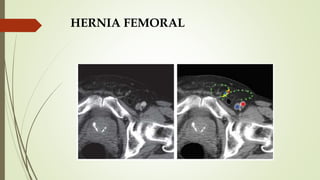

HERNIA FEMORAL

 SINÓNIMOS: Hernia crural, enteromerocele,

femorocele.

 Protrusión de contenido intraabdominal a lo largo de la

vaina femoral en el canal femoral, medial a la vena

femoral.

 Defecto congénito en la inserción de la fascia

transversalis en la rama iliopubiana.

 Se asocia a aumento de la presión intraabdominal.

 36% en pacientes mayores de 80 años.

 Predominantemente mujeres.

 Clinica: Inflamación, dolor, sensación de movimiento en

la ingle, abultamiento en l parte alta del muslo.

 Náusea, vómito si hay estrangulación.

 HALLAZGOS DE TC:

 Mejor prueba de imagen.

 Grasa epiploica o intestino se hernian hacia el canal

femoral mediales a la vena femoral.

 Saco herniario posterior al plano horizontal del

tubérculo del pubis.